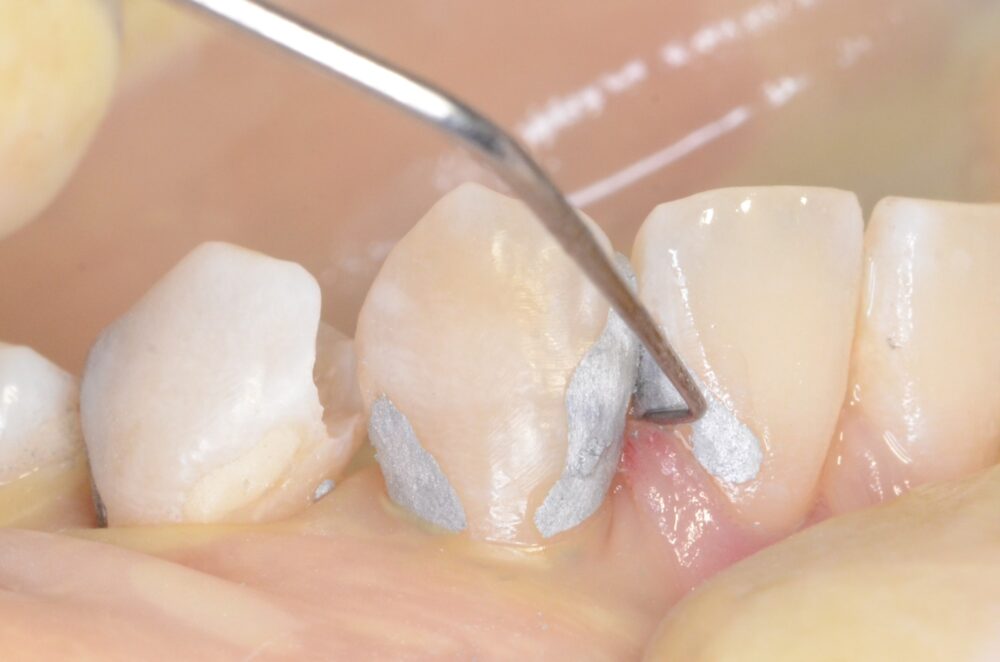

上の写真は適切に充てんされたアマルガム充填の例です。アマルガムが他の材料と比較して優れている理由には次の3つがあります。

まず、虫歯は必ず下掘れになっているため、インレーなどの修復材料では歯を多く削りすぎてしまうからです。歯を削りすぎると、かみ合わせの面を人工的に作らなければならず、かみ合わせを狂わせてしまう可能性が大きくなるからです。アマルガムはかみ合わせの面の歯の切削量を最小限にしてくれます。

次に、臼歯部には強い咬合力(噛む力)が加わるため、十分な強度が必要になります。最近よくつかわれるレジン(樹脂)は、見た目は白くてよいのですが、強度が咬合力に対して不十分であったり、吸水性(水を吸う性質)があったり、材料自体に抗菌性がありません。一方アマルガムには、金属としての十分の強度と、強い抗菌性があるため、虫歯が拡大しにくいのです。

最後にアマルガムには歯に詰めた後に膨張する性質があるため、歯に完全に適合し、歯と材料との間に空間(死腔と呼ばれる)を作ることがなく、虫歯の再発が極めて少ないです。ただ水銀が含まれている(無機水銀ですので人体には安全です)環境への問題から使用しない人もいますが、歯を長持ちさせるためには今でも欠かせない材料です。